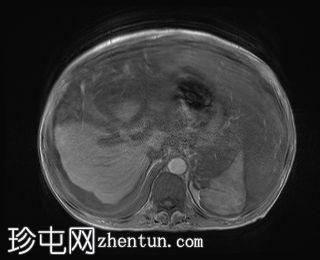

轴向

T2

升结肠壁增厚,尤其前壁,形成肿块,T2信号高,提示其为黏液性肿块。肿块无扩散受限,增强扫描后几乎无强化。

腹腔内可见大量T2信号高、T1信号低至中等的包裹性积液,与腹膜凹陷相符,并导致内脏表面(尤其是肝脏和脾脏)呈扇贝状。这些表现是腹膜假黏液瘤的特征性表现,可能由黏液性肿瘤播散引起。